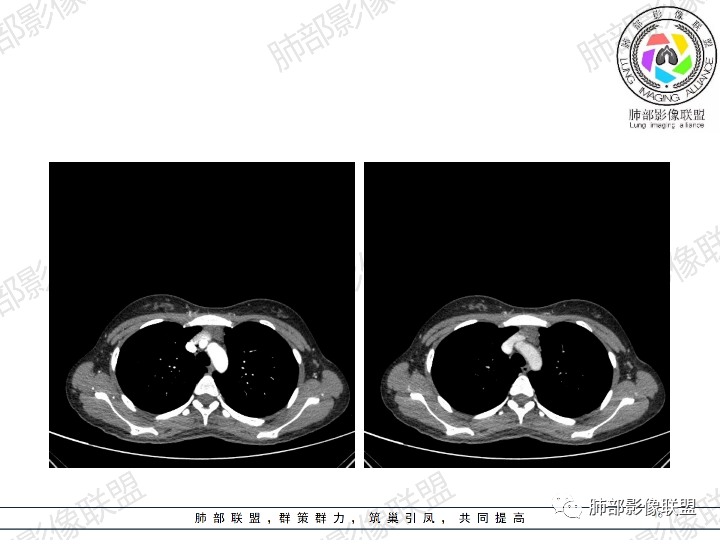

影像:前纵隔一实性肿块,形态不规则,沿主动脉间隙生长,部分包绕大血管,边界欠清,周围脂肪间隙消失,平扫密度尚均匀,增强扫描大部分强化不明显,病灶左下部分似有高强化,强化病灶与血管分界清楚,考虑:1淋巴瘤(一般居中,病灶较软,包绕血管)

女性,23岁,体检发现纵隔占位。CT示前纵隔不规则占位,沿间隙生长,局部包绕大血管及心包,增强内部可见部分区域呈明显渐进性强化,其余部分强化不明显,考虑囊性畸胎瘤或神经鞘瘤>淋巴瘤,太年轻不考虑胸腺瘤

影像:前纵隔偏左侧团块影,增强扫描呈结节强化伴周围低/无强化。

青年女性患者,体检发现左前纵隔占位性病变,胸部CT:左前纵隔见一不规则占位性病变,整体边界清楚,紧贴血管,间隙不明显,内部密度尚均匀,未见钙化及脂肪密度,增强扫描不均匀轻度强化,总体考虑偏良性病变,胸腺增生?

这个病灶有点怪

1、形态,似乎与常规肿瘤不一致

2、有间隔

3、密度强化有点怪

这些边缘收缩

符合胸腺正常形态

倾向于:一个正常增大的腺体内的病变

根据部位:腺体首先考虑胸腺,其次才考虑异位结构

胸腺内囊、实性占位

首先支持胸腺增生并感染

其次胸腺瘤

然后才考虑异位的病变

这个病例的特点就是病灶整体符合胸腺的形态,如果它是肿瘤,它周围侵袭性不明确的话,它应该膨隆的挺厉害,它单纯就是一个膨隆性生长的,那么它就应该是类圆形的,边缘应该是膨大的,但是这个病例不是,有些地方边缘是收缩的,那么就是原有的胸腺基础上内部出了问题,里面强化增生明显就有可能是在原有胸腺基础上里面滋生出来一个病变。年龄确实年轻,又是女性。胸腺里面的病例多是胸腺瘤、胸腺癌、淋巴瘤。既然定的是胸腺里面的病变,那么就在这里面考虑。淋巴瘤首先不是。那么就是胸腺瘤和胸腺增生,胸腺囊肿的说法也有很多,因为胸腺增生里面有一种就是囊性的增生,里面有些地方有强化,囊肿合并感染了可以有,慢性炎性的肉芽肿的可以有强化。不能排除胸腺瘤,胸腺瘤放后面,一个原因就是太年轻了。如果考虑胸腺瘤,年龄不太符合,心里不踏实。我认为大家不考虑胸腺瘤是正常的思维,写报告也是待排,放第一诊断不合适。考虑有胸腺瘤是因为强化,占位效应,间隔。